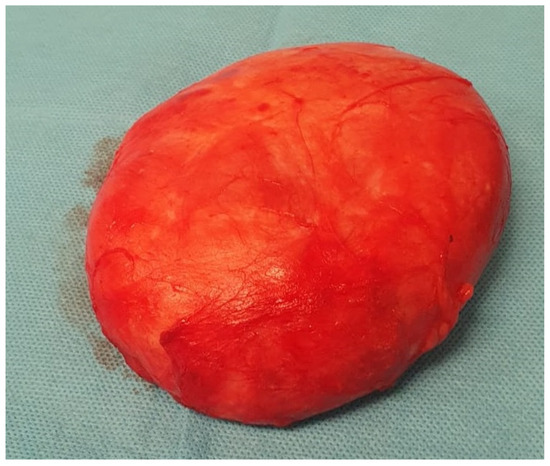

The histopathological examination confirmed the diagnosis of pseudoangiomatous stromal hyperplasia (PASH). The specimen was described as a solid, light gray-to-yellow tumor measuring 11 × 10 × 4.8 cm3, with the capsule preserved and intact (Figure 2 and Figure 3).

Figure 2. Resected surgical specimen.